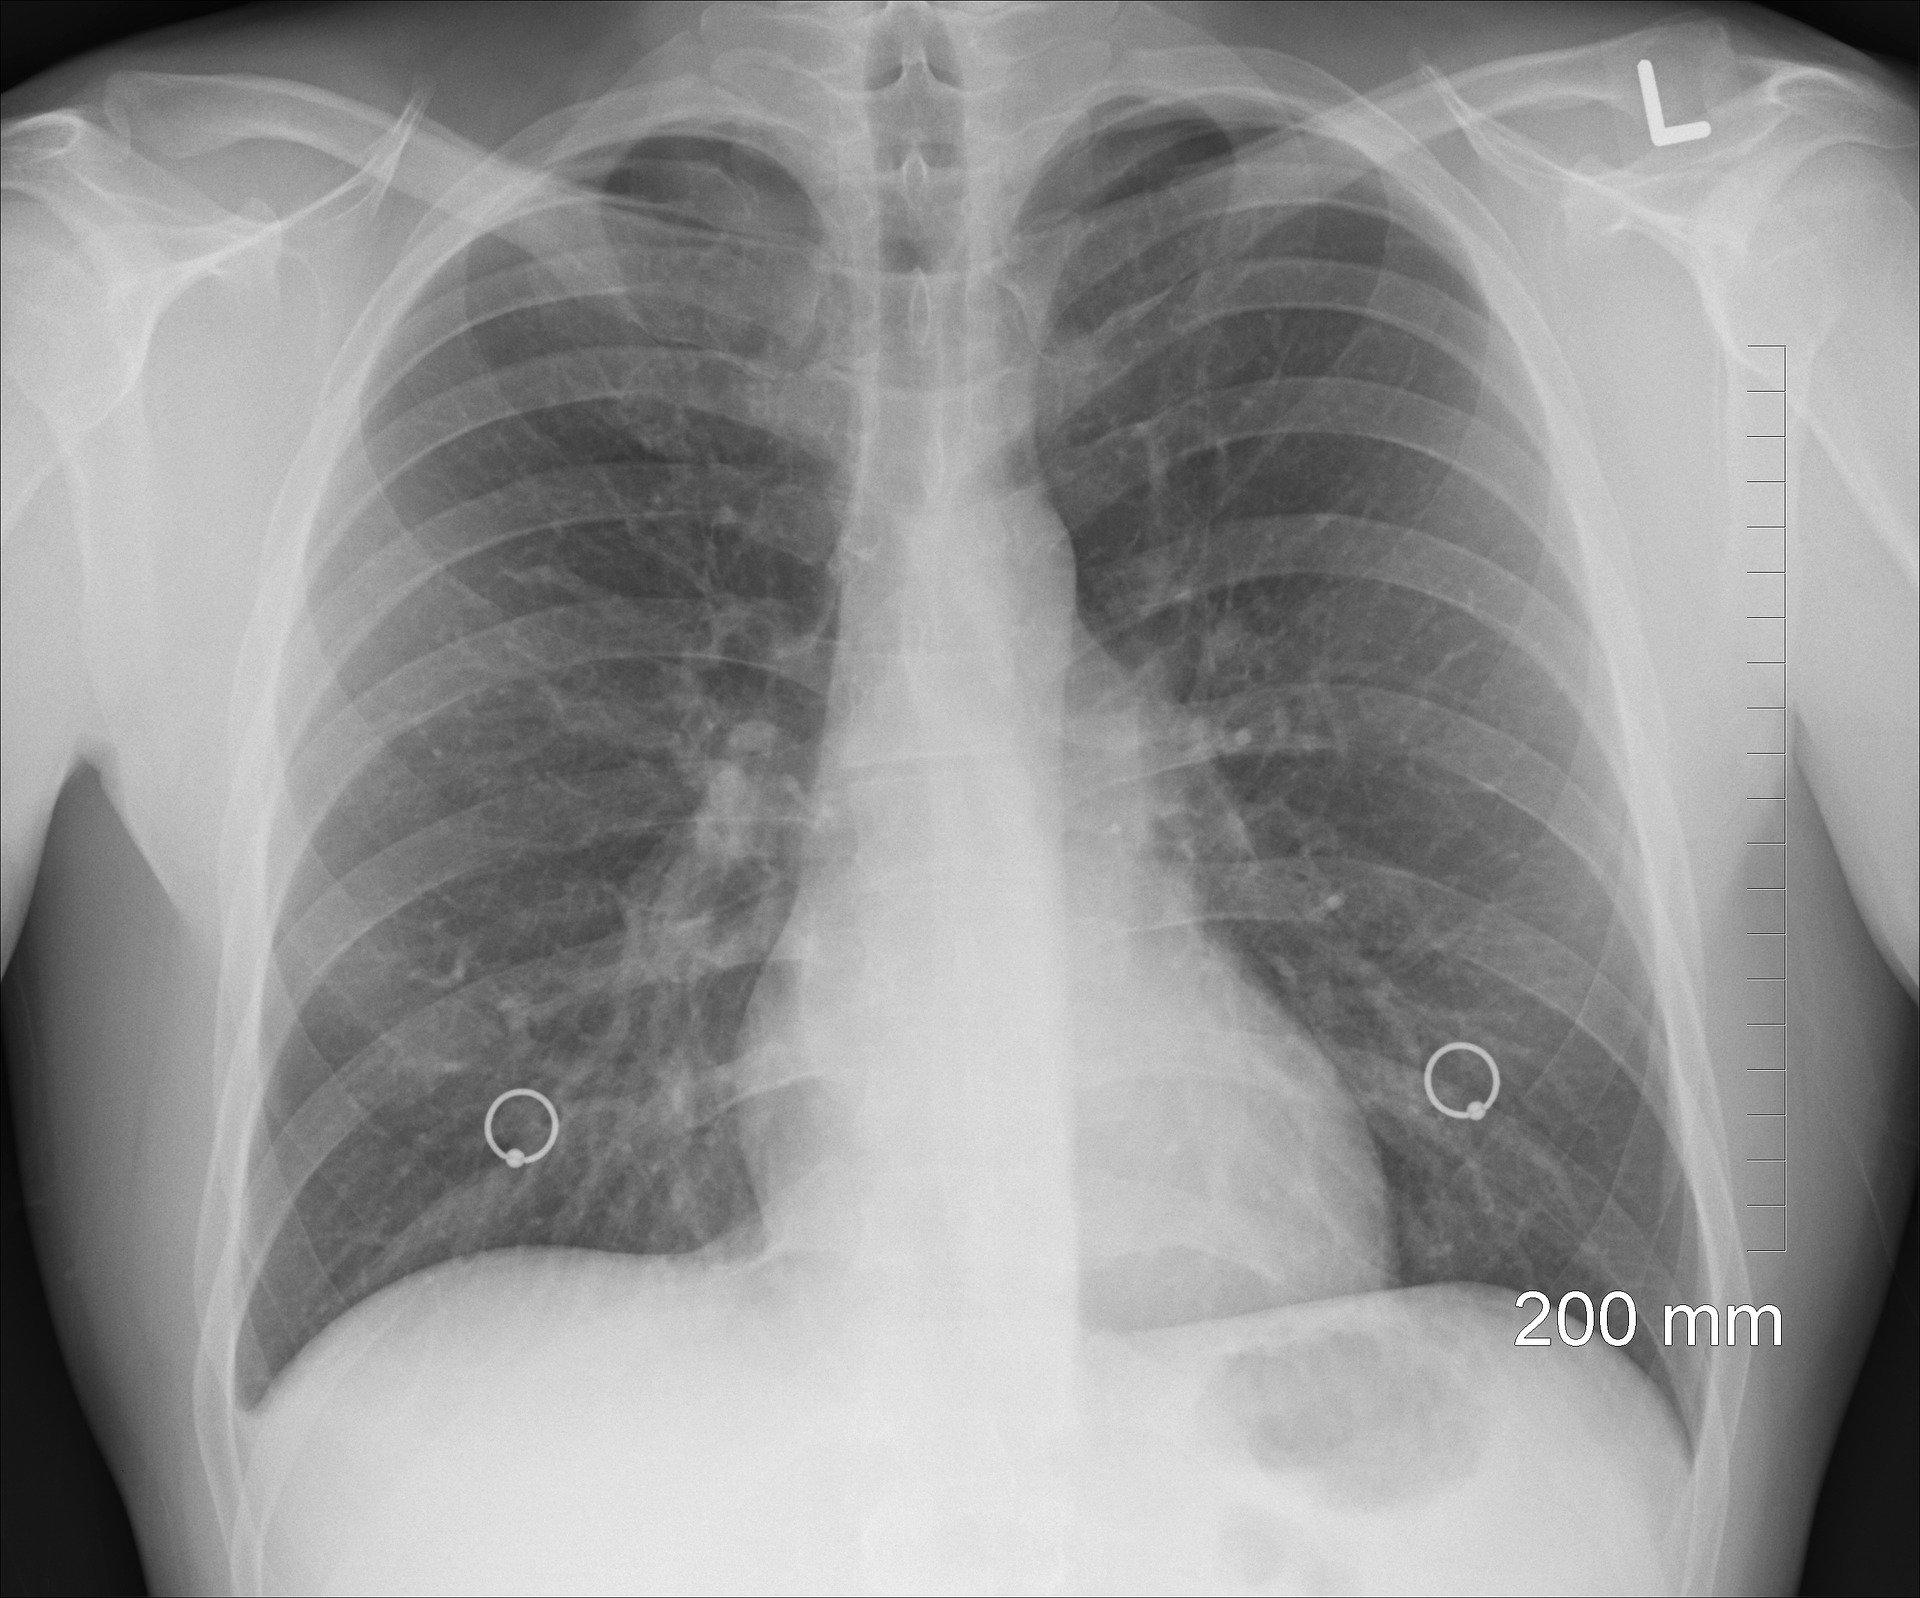

Lung cancer is one of the most common and deadliest types of cancer, afflicting millions of people across the globe annually. The first scientific study associating pesticide exposure with lung cancer occurred 50 years ago and, ever since, epidemiological studies present increasing evidence that pesticide exposure increases the risk of developing lung cancer. A 2004 study demonstrates a positive association between lung cancer and seven widely used agricultural pesticides (e.g., dicamba, metolachlor, pendimethalin, carbofuran, chlorpyrifos, diazinon, and dieldrin). Likewise, a U.S. study finds that the risk of developing lung cancer increases with the number of years working as a pesticide applicator. This study adds to the growing body of research linking pesticide use and exposure to various forms of cancer.

The connection between pesticides and associated cancer risks is nothing new, as a plethora of studies links pesticide use and residue to various cancers, from more prevalent forms like breast cancer to rare forms like kidney cancer nephroblastoma (Wilms’ tumor). The connection between lung cancer and pesticides is of specific concern, as etiological studies often attribute lung cancer to genetics or cigarette smoke and overlook the lung cancer risks associated with pesticide exposure via inhalation of powders, airborne droplets, or vapors. Some studies attribute pesticides—labeled hazardous to inhale—sprayed on tobacco plants to lung cancer, and the related mechanisms that cause lung cancer. Upon inhalation, pesticide particles enter the respiratory tract, and the lungs readily absorb the particles into the bloodstream.